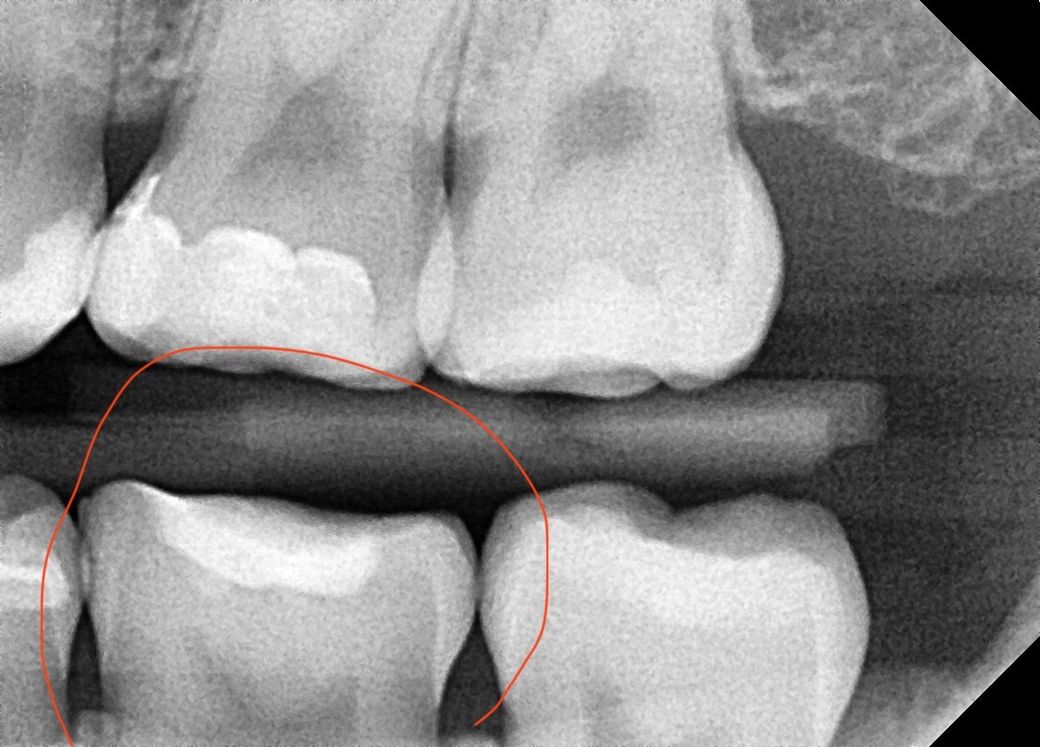

어금니 인레이 치료를 받았습니다 (아래 왼쪽 뒤에서 두번째 어금니)

1년동안 탈없이 잘 사용했는데 며칠전부터 자꾸 치아가 시립니다 가만히 있을때에도 은은하게 시리고 식사할때도 은은하게 시리는데 막 아프다 정도는 아닙니다

다만 잘못되었을까 걱정되네요 치아가 시리기전에 치과 검진을 갔었는데 (3주전) 그때는 별말씀 없으셨습니다.. 왜 시린건가요?.. 충치가생긴걸까요 아니면 인레이 틈이생긴걸까요?

컨디션이 안좋으면 며칠 일시적으로 그럴순 있습니다 일단 지켜보시고 증상이 심해지면 다시 치과 가보세요 지금 사진상으론 별다른 문제가 보이진 않습니다